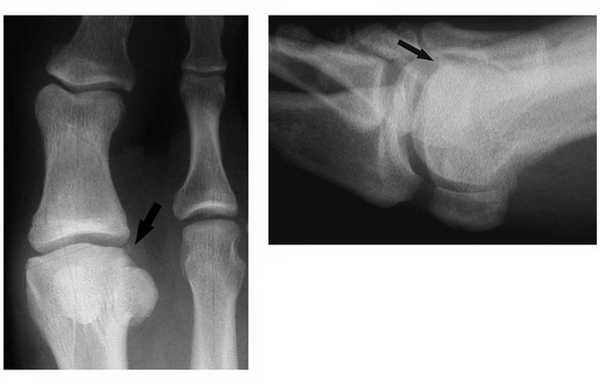

Расхождение обеих сесамовидных костей у спортсмена. А, Рентгенограмма до травмы — картина удвоения обеих сесамовидных костей. В, Рентгенограмма после травмы — отмечается расхождение фрагментов обеих сесамовидных костей. С, Рентгенограмма этого же пациента в боковой проекции.